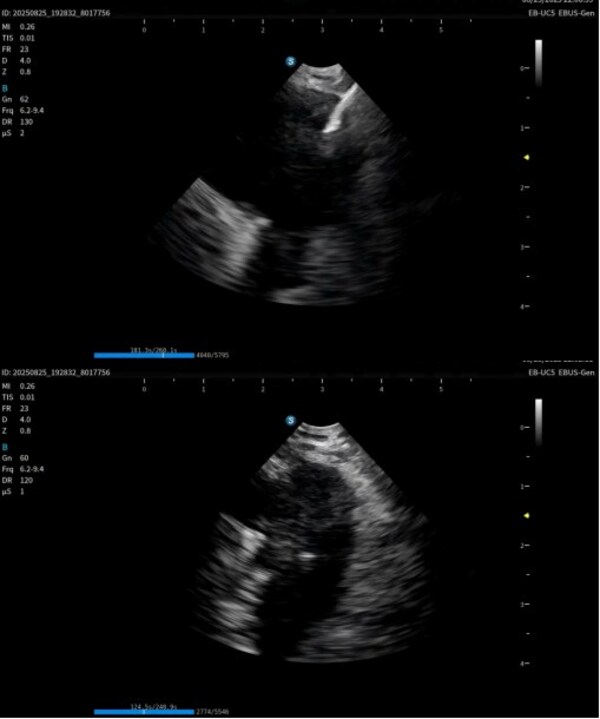

作為在呼吸診療領(lǐng)域的重磅產(chǎn)品,本次在產(chǎn)品創(chuàng)新設(shè)計上和工藝技術(shù)上取得了重大突破,顯著提升了光學(xué)圖像和超聲圖像的質(zhì)量,同時鏡體保持了良好的操作性,在鉗鏡比和視野角綜合參數(shù)可達(dá)到全球同類產(chǎn)品最佳性能。目前在臨床應(yīng)用表現(xiàn)突出,取得了專家的認(rèn)可和好評。

超聲電子支氣管內(nèi)窺鏡憑借其"微創(chuàng)、精準(zhǔn)、安全"的特點,已成為呼吸介入領(lǐng)域的核心技術(shù)之一。開立醫(yī)療全系列產(chǎn)品全面上市可為肺部腫瘤、縱隔病變提供管內(nèi)清晰光學(xué)影像,管外高清聲學(xué)斷層組織及血流影像,提供精準(zhǔn)可視化介入操作,為疾病的診斷提供更精準(zhǔn)、更安全、更高效的一體化診療解決方案。